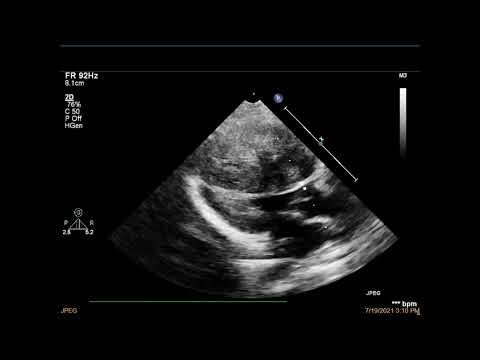

Протокол ЭхоКГ у детей парастернальная проекция, длинная ось левого желудочка Часть I (рус. перевод)